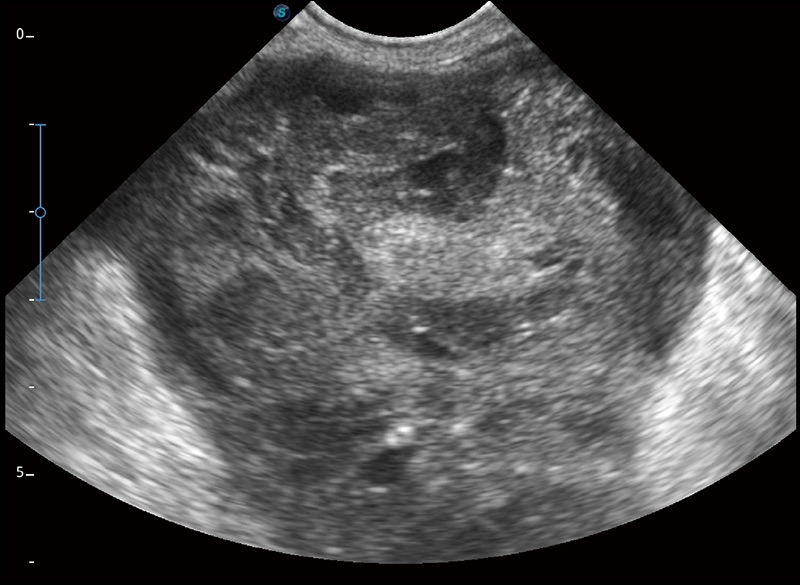

α1卓越的图像质量和便捷的工作流程,使每位宠物医生都能轻松扫查。其全面的兽用应用功能和紧凑型的结构设计,可以满足动物检查的多种需要。专业的预设检查模式和多领域测量软件包有助于为不同类型的动物提供检查, 让宠物医生能够出色的完成工作。

任意波束合成技术

在不牺牲时间分辨率的情况下提供出色的图像

空间复合成像

优化不同角度的图像

扩展成像

支持线阵和凸阵探头,一键操作即可获得更宽的图像视野

实时宽景成像

可实时观察感兴趣区域和病变位置